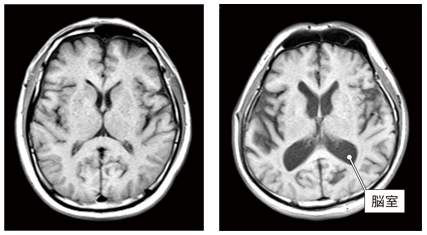

脳の萎縮

この画像はともに50代の人の脳です。

右の人は脳室(中心にある黒いエリア)が左に比べ拡大しており、脳の萎縮が進んでいると判断されます。

萎縮は脳の機能低下や認知症発症のリスク因子です。

60歳を過ぎても30代並みの若々しい脳を保っている方の例も多くあり、加齢による萎縮の進み方は人によって大きく異なります。